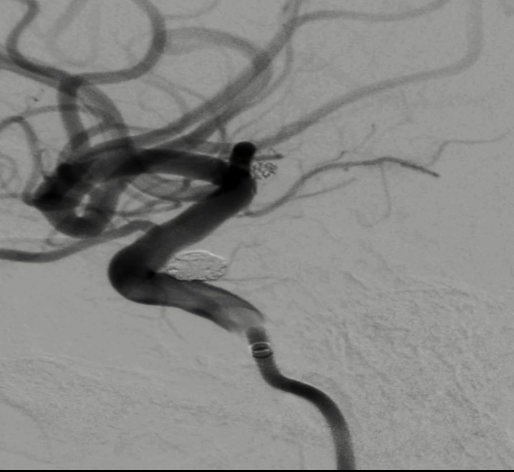

治疗结果

术后正侧位造影:Raymond Ⅲ级

术后支架重建:支架打开良好,近端Marker位于颈内动脉分叉处

术后Vaso CT未见出血,患者神清语利,神经系统查体阴性。